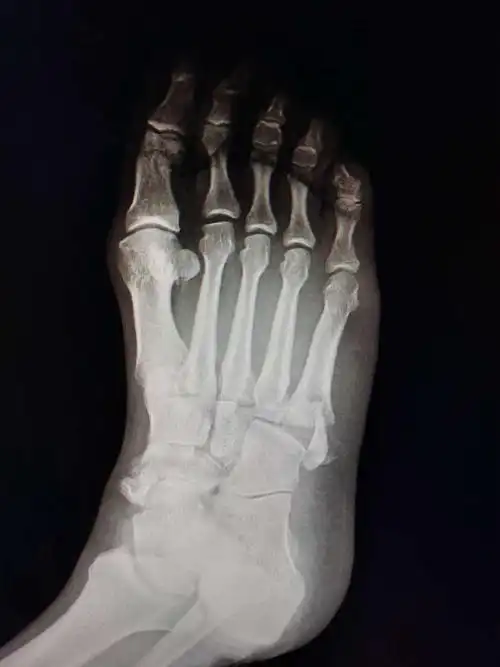

一例足舟骨第五跖骨基底粉碎性骨折的治疗